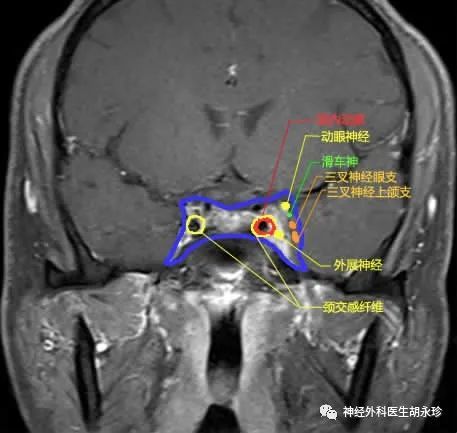

交感神经通路自下丘脑发出后经过脑干、颈髓下降至C8、T2 脊髓侧角换元( 中枢/第1 级神经元) ;第2 级神经元发出后离开颈髓沿颈部交感神经链向下走行至锁骨下动脉附近 , 向上折返 , 到达颈动脉分叉处的颈上神经节( 颈2 ~ 3 水平) 再次换元( 节前神经/第2 级神经元);换元后的节后神经纤维缠绕颈内动脉壁进入颅内、海绵窦 , 最后随眼神经( 三叉神经第1 支) 进入眼眶 , 支配眼睑Müller肌、瞳孔扩大肌( 节后神经/第3 级神经元)。

(3) 第3 级神经元(节后神经):颈内静脉扩张、颈内动脉夹层动脉瘤、海绵窦炎症/肿瘤、眼眶内病变均为节后神经霍纳综合征损害的常见病因 。 由于颈内动脉夹层动脉瘤最为风险 , 尤其是在急性发生的霍纳综合征伴有面部疼痛且向颈部放散时需要进行紧急排查 。

神经系统伴随症状:单侧的Horner综合征(中枢性)伴有对侧上斜肌麻痹(滑车神经)提示损害位于滑车神经核或脑干神经簇(滑车神经核为交叉支配) 。 单侧Horner综合征(节后段)伴同侧展神经麻痹 , 提示海绵窦病变 。 Horner综合征伴对侧肢体运动障碍提示半球或脑干病变;Horner伴上肢麻木提示颈段损害 。 急性、疼痛性Horner综合征(尤其是第3级损害)近60%为颈内动脉夹层动脉瘤导致 , 需要进行紧急排查 , 否则患者将有脑梗死的风险 。